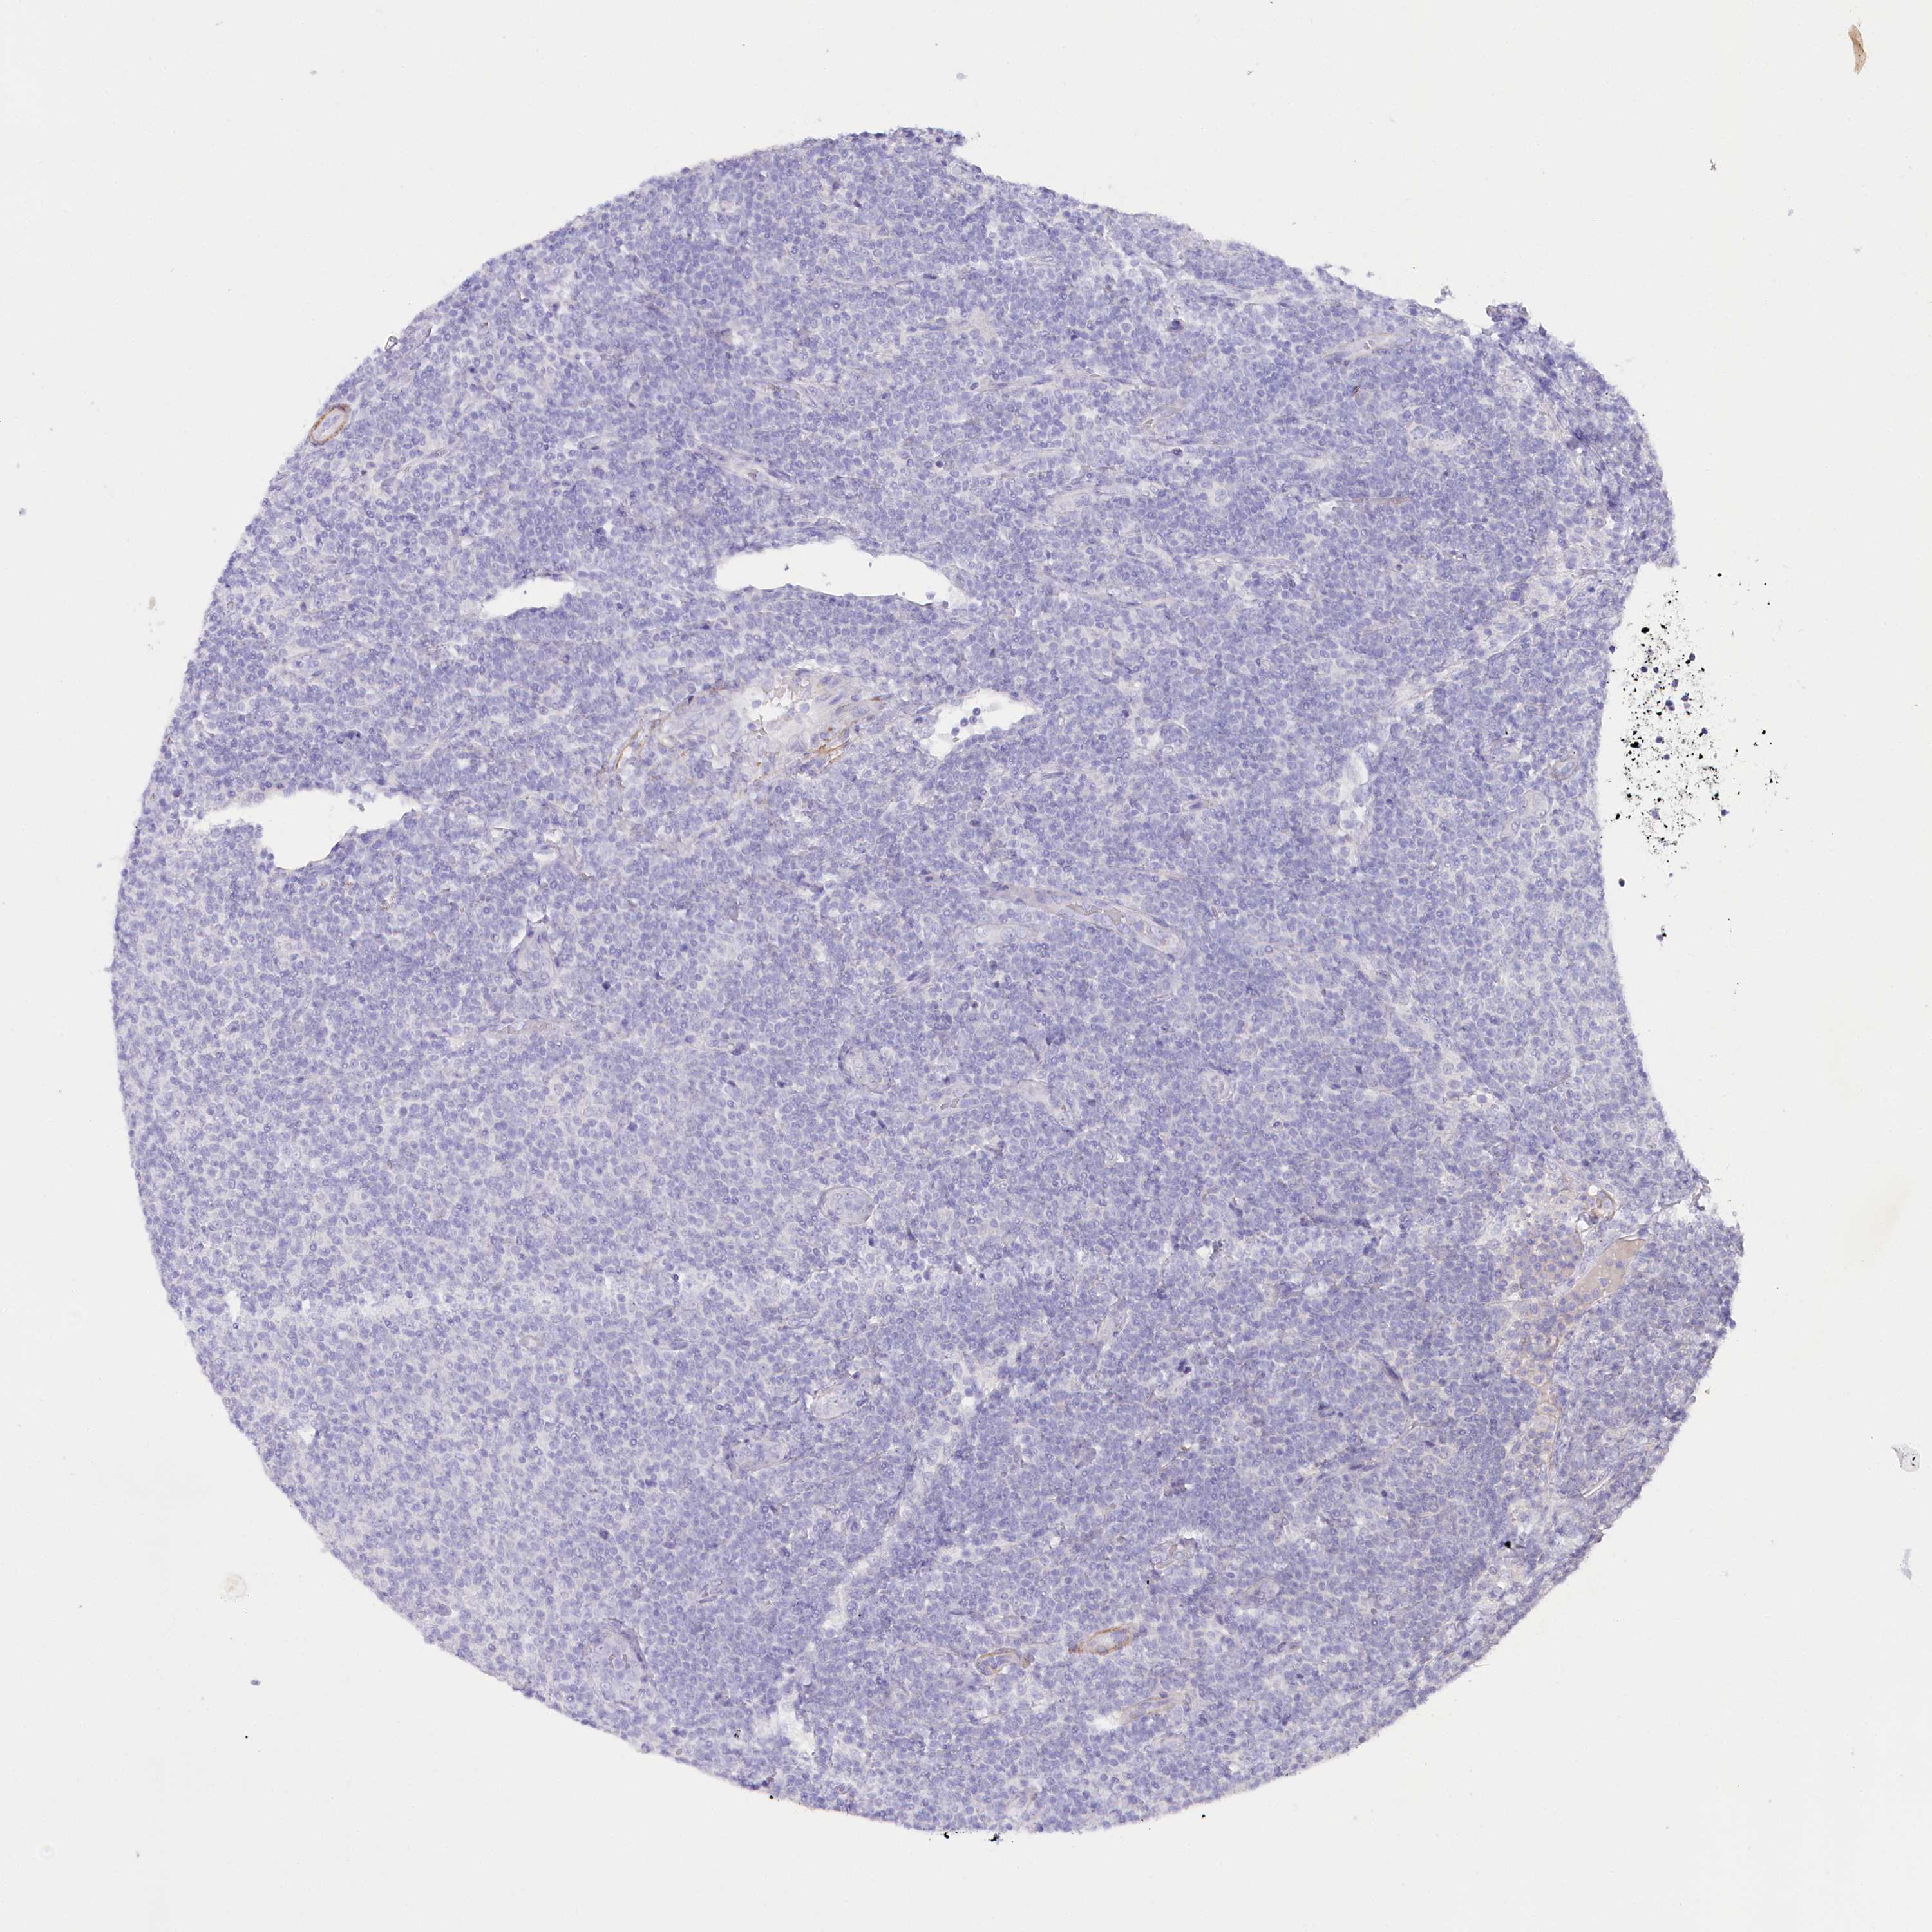

CANCER LYMPHOMA Show tissue menu

LYMPHOMA - Protein expressioni

A mouse-over function shows sample information and annotation data. Click on an image to view it in a full screen mode. Samples can be filtered based on level of antibody staining by selecting one or several of the following categories: high, medium, low and not detected. The assay and annotation is described here.

Each image is clickable and will lead to virtual microscopy that enables deeper exploration of all samples and also displays staining intensity scores, fraction scores and subcellular localization as well as patient and tissue information for each sample.

Antibody HPA035953

Hodgkin's disease, NOS

Malignant lymphoma, non-Hodgkin's type, High grade

Malignant lymphoma, non-Hodgkin's type, Low grade